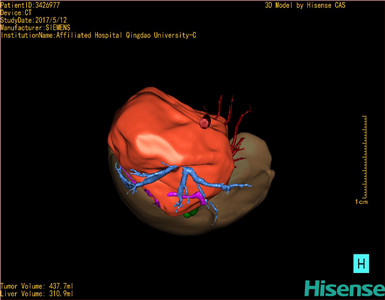

CT结果输入海信CAS系统后行3D重建及手术规划后,肿瘤位于右肾上腺区并周围淋巴结肿大,与血管关系紧密,建议化疗,静脉高营养、全量补液及对症支持治疗,患儿恢复良好,伤口无渗血渗液,无红肿疼痛,于2017-5-16出院。

术前三维重建:

重建图片